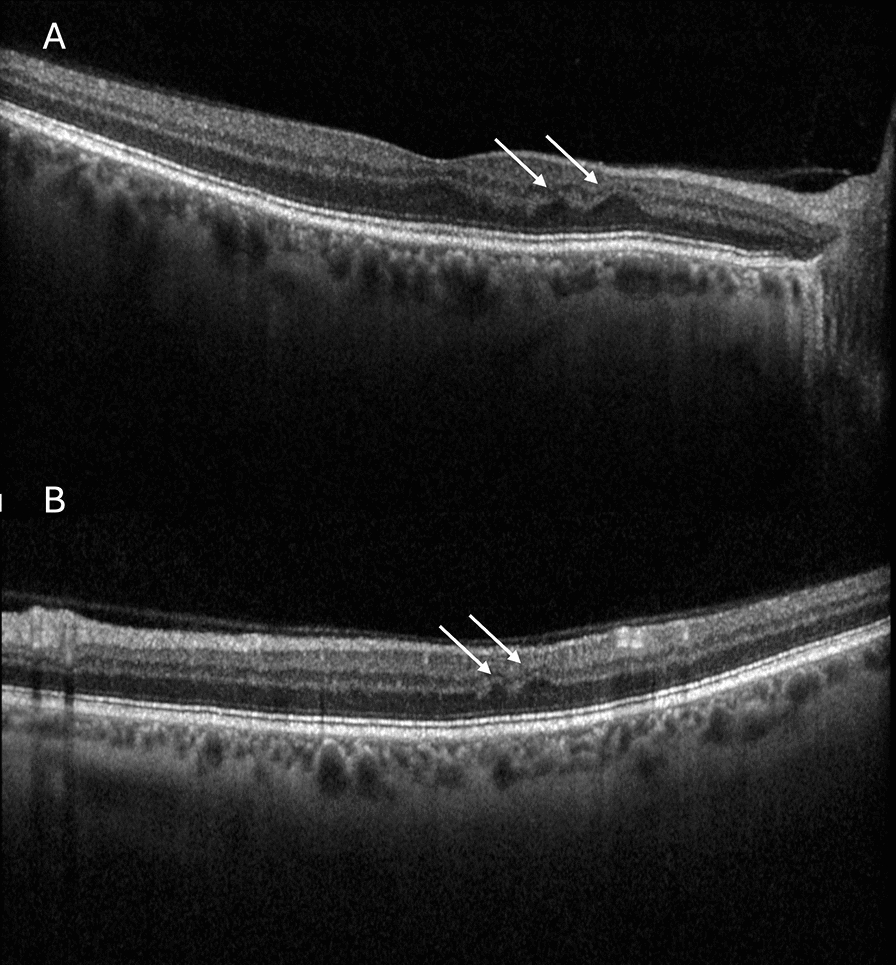

The initial hyperreflective PAMM lesions gradually evolve into corresponding retinal ischemic perivascular lesions (RIPLs) [12]. RIPLs refer to a characteristic focal thinning of the inner nuclear layer (INL) with a compensatory upward expansion of the outer nuclear layer (ONL), resulting in a wavy appearance of the middle layers of the retina [12] (Fig. 1).

A, B Spectral-domain optical coherence tomography (SD-OCT) scans of an asymptomatic 67-year-old male patient, illustrating retinal ischemic perivascular lesions (RIPLs) (white arrows), which were found incidentally during routine eye examinations. Best-corrected visual acuity is 20/30 in both eyes. RIPLs refer to characteristic focal thinning of the inner nuclear layer (INL), with compensatory upward expansion of the outer nuclear layer (ONL), resulting in a focal wavy appearance of the middle retinal layers